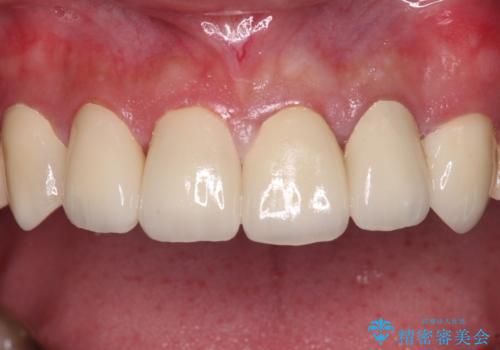

むし歯は多かったものの、歯肉の腫脹はそれほどなかったため、最小限の治療回数で治療を終えることができました。